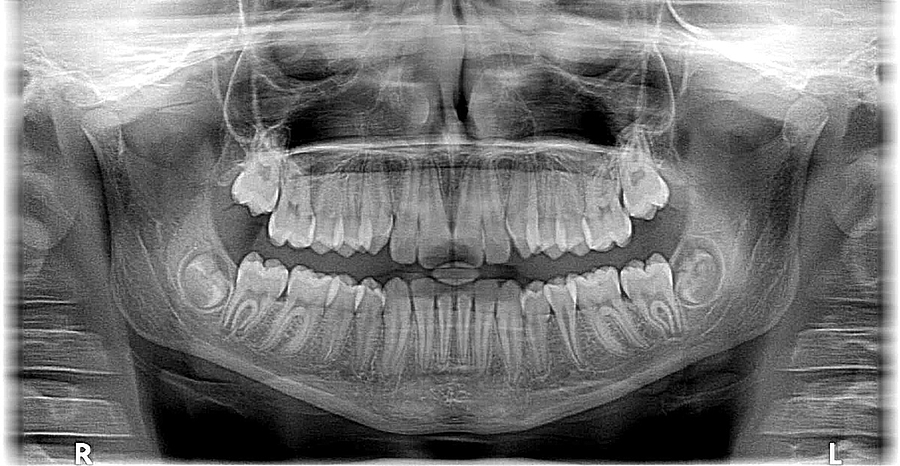

Seit dem Jahreswechsel sind Arztpraxen und Kliniken nicht mehr gesetzlich verpflichtet, Patientinnen und Patienten einen Röntgenpass zur Verfügung zu stellen und Röntgenuntersuchungen in einen solchen einzutragen. Das Bundesamt für Strahlenschutz (BfS) rät dennoch dazu, über erhaltene strahlendiagnostische Untersuchungen Buch zu führen. Dies umfasst Röntgen-, aber auch nuklearmedizinische Anwendungen.